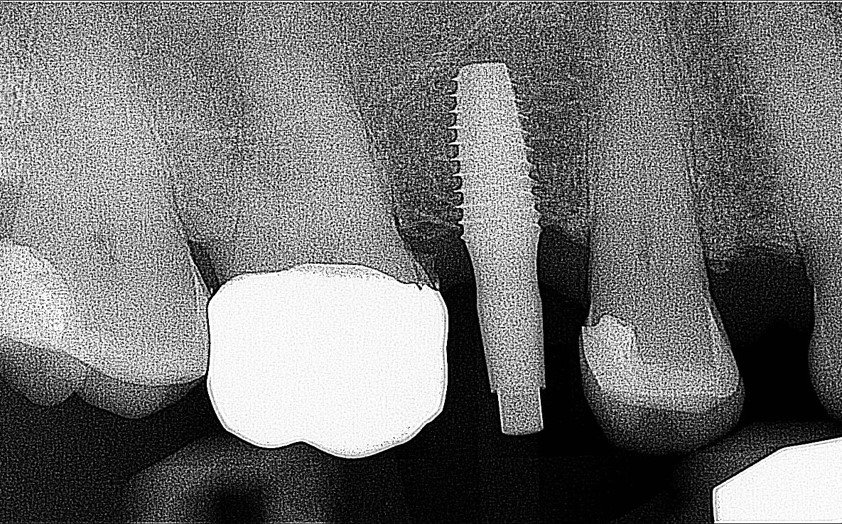

A dental Implant is a titanium “root” that integrates directly with the surrounding bone and replaces the function of the natural tooth. Neoss Implants are made using the best quality medical grade titanium, which is well known for its proven biocompatibility, and have a treated surface to facilitate bone integration.